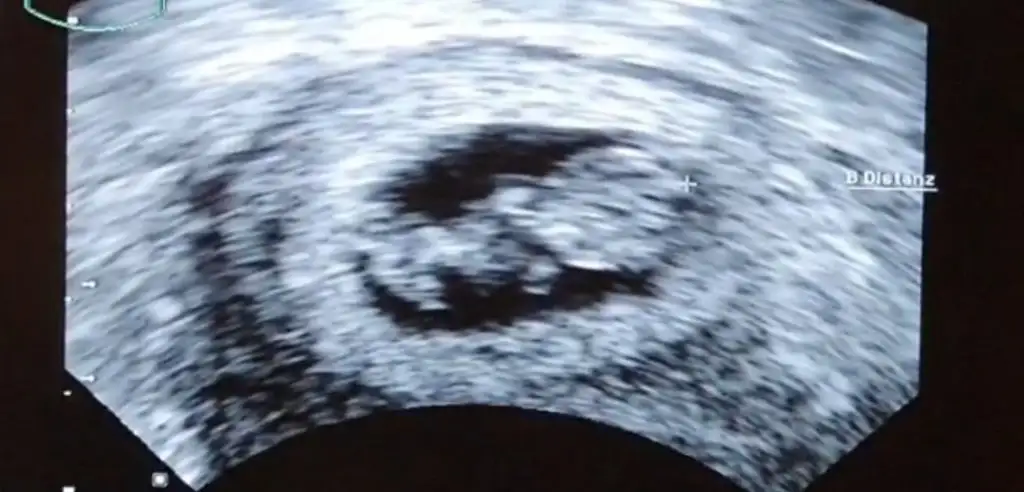

İlk ultrason resmine göre cinsiyet tahmini

Eklentiler

• IMG_20220225_081759.webp

IMG_20220225_081759.webp

16,2 KB · Görüntüleme: 594